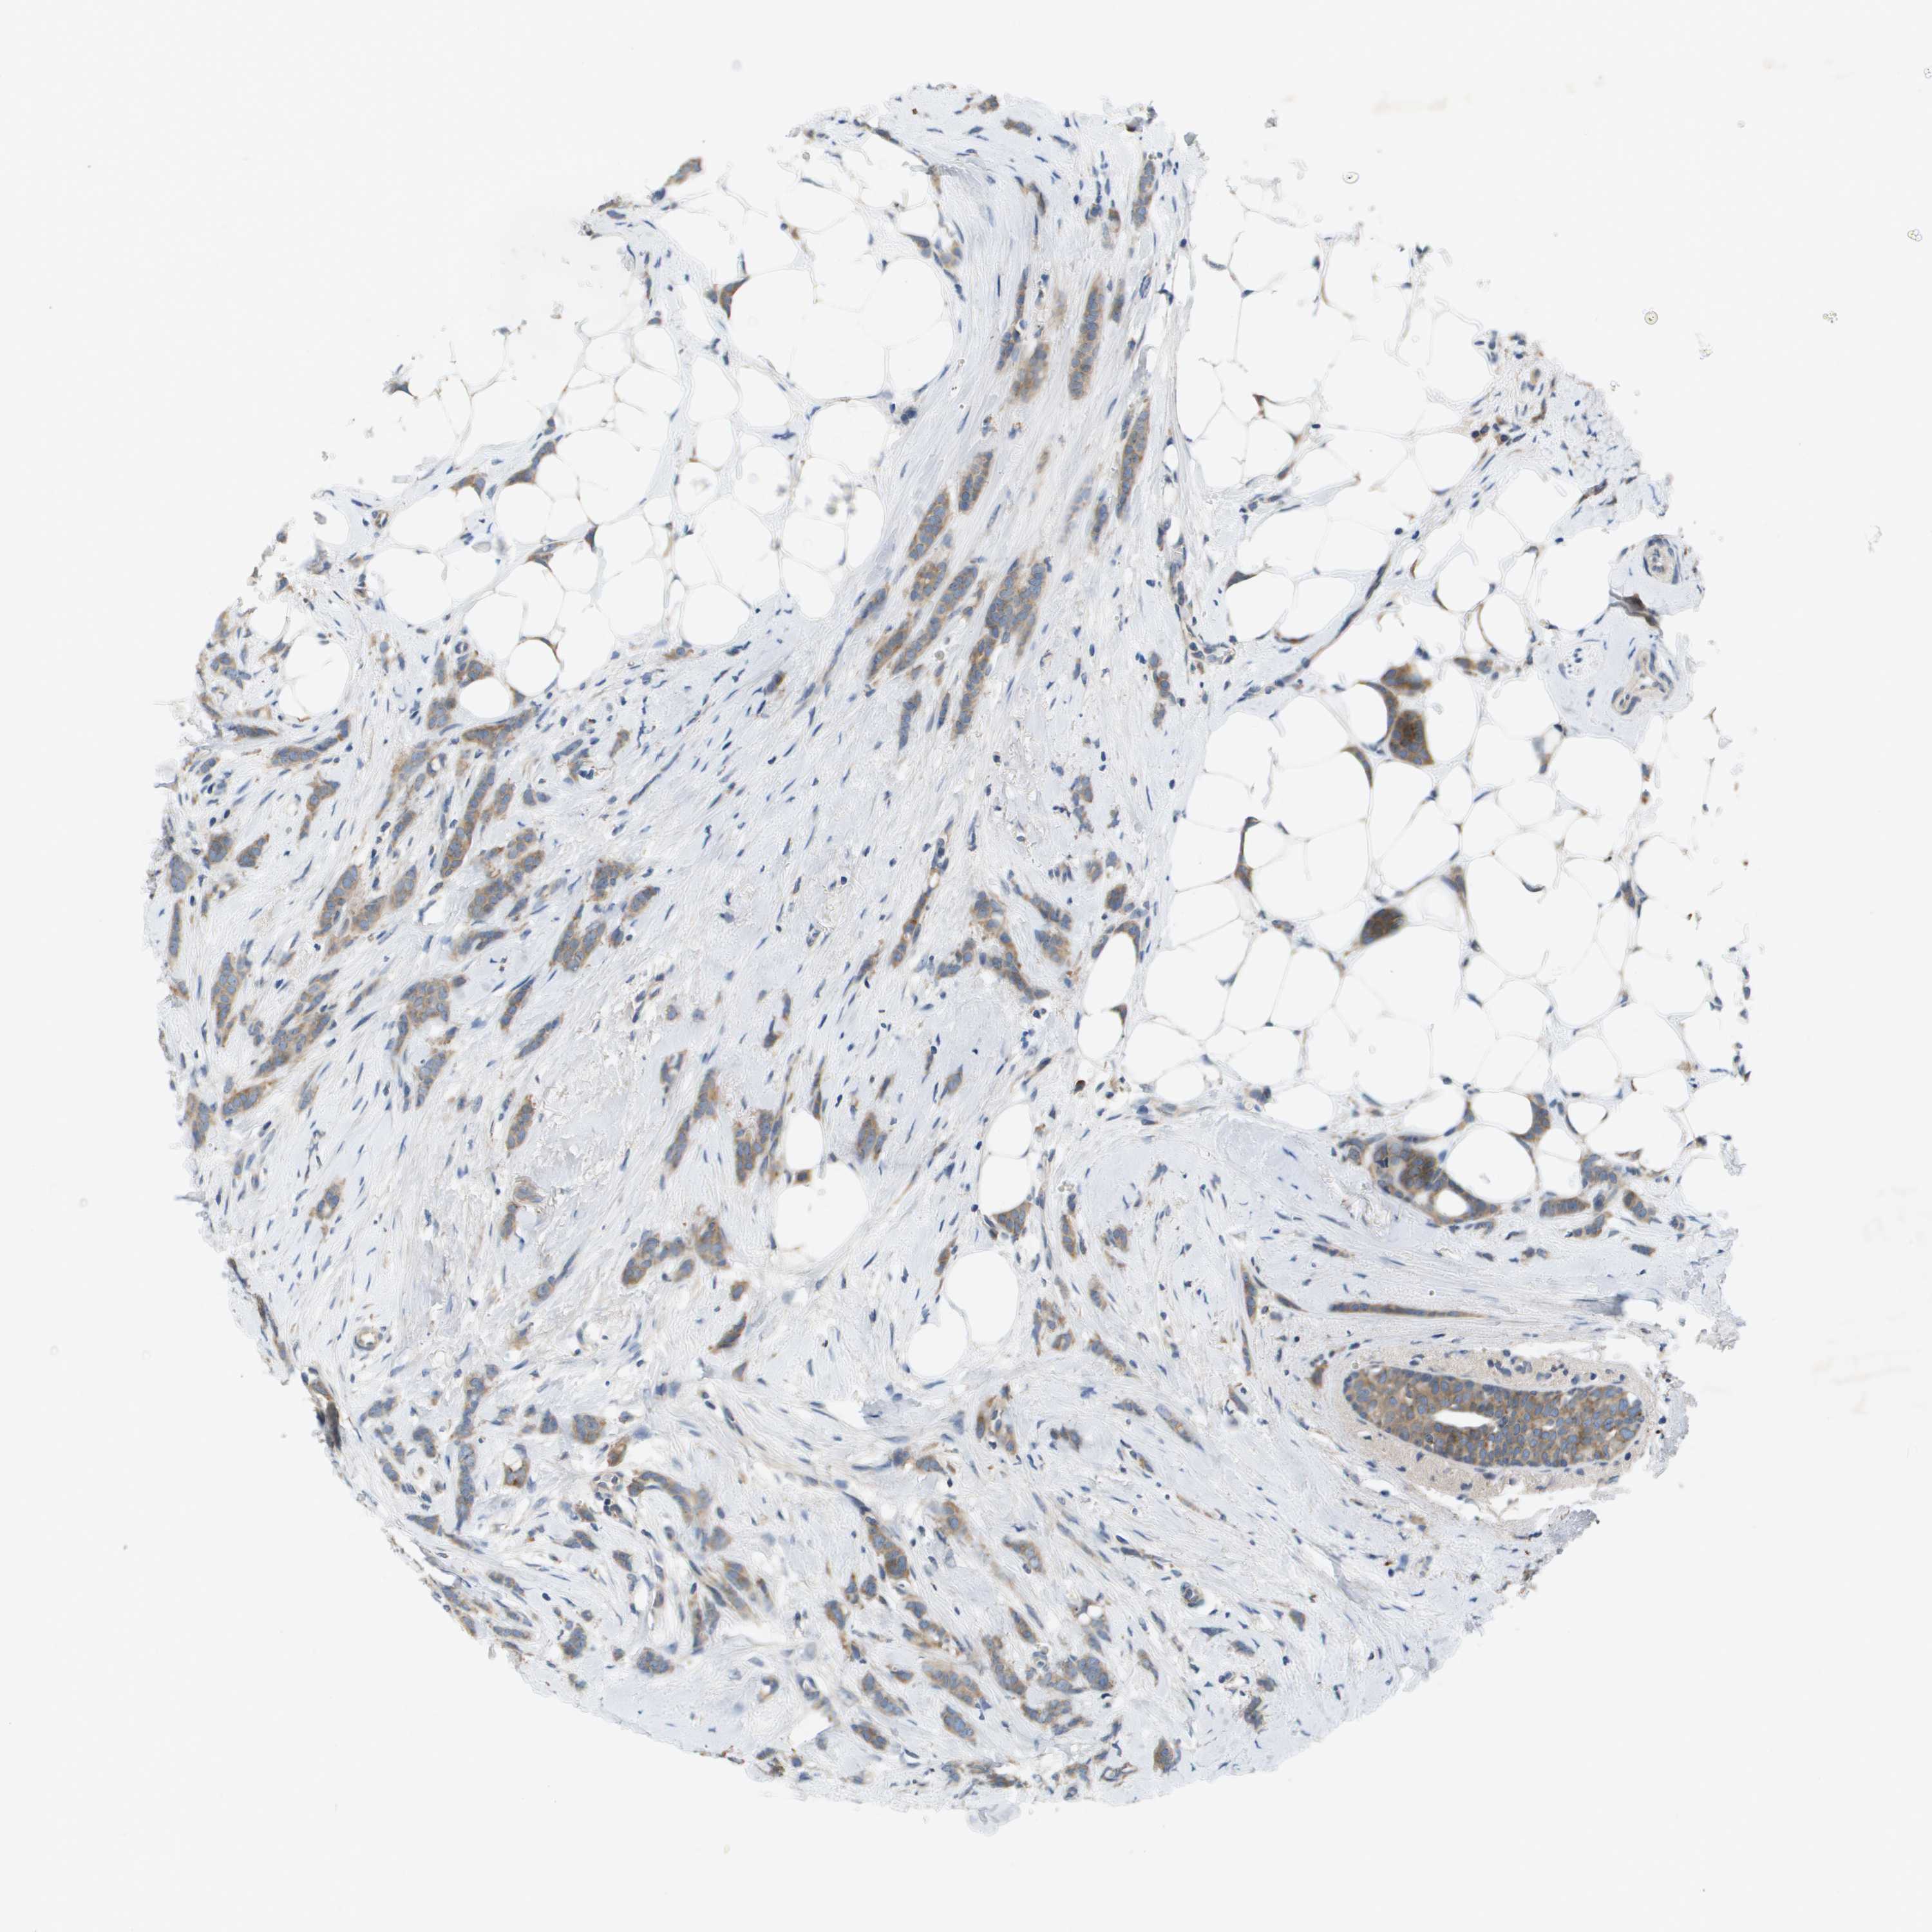

BRCA TCGA BRCA VALIDATION PROTEIN EXPRESSION

ANTIBODIES

AND

VALIDATION